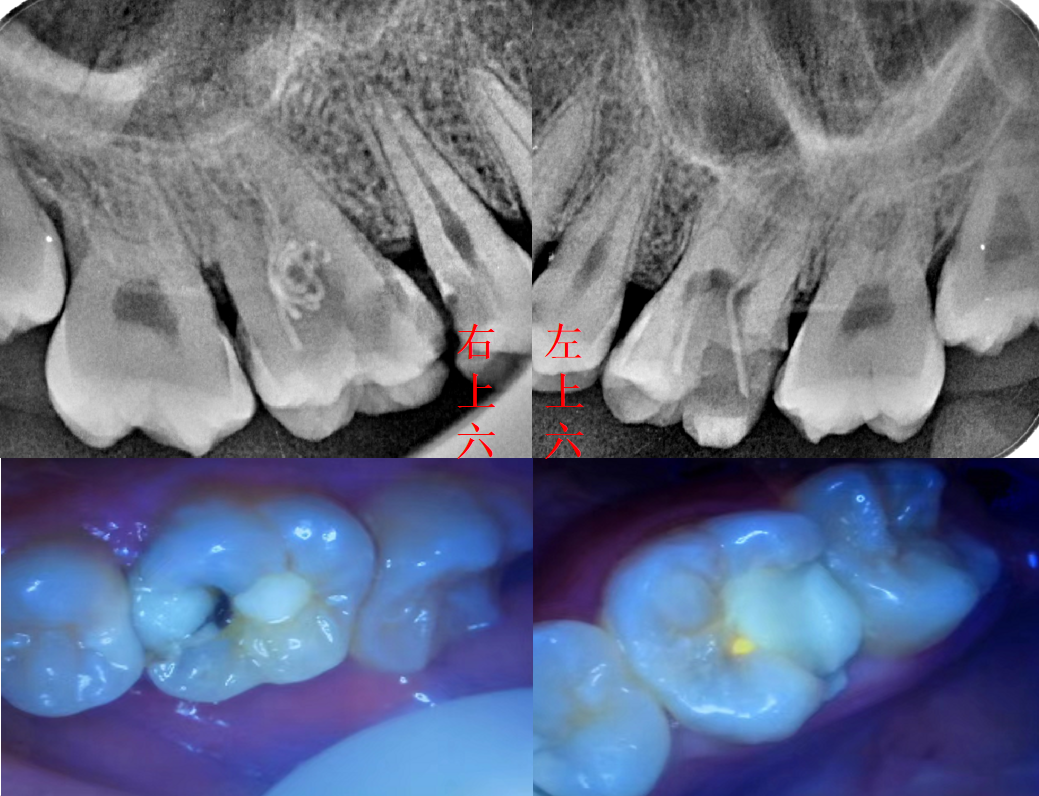

六号牙医 的想法: 左上六号牙,右上六号牙,两颗外院做的根… - 知乎

效果良好,完美的避免了拔除6号牙以后得种植牙或镶牙问题!

准备根充,主牙胶尖定位,发现近中根管未找到(为了视觉效果全部片子和